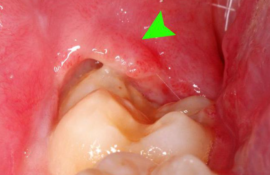

расположение зубов мудрости в десневом кармане

Неполное прорезывание приводит к формированию десневого капюшона – складки десны над зубом. Особенностью этого образования является то, что в него часто набивается пища, которую очень сложно вычистить зубной щеткой.

При обсеменении остатков пищи микроорганизмами развивается очень неприятное заболевание – перикоронарит.

- Иногда прорезывающийся зуб накрывает своеобразный «капюшон» из разросшейся слизистой. Под ним скапливаются остатки пищи и размножаются бактерии.

Этот процесс приводит не только к болезненности и отеку. Появляется неприятный запах изо рта и затруднение при глотании.

После еды там скапливаются остатки пищи, а при обычных гигиенических процедурах удалить их оттуда очень сложно. Поэтому в этом кармане развиваются бактерии, вызывающие воспалительный процесс.

У некоторых людей он протекает почти безболезненно и проходит сам. Но довольно часто появляются различные осложнения. Во время жевания десна может повредиться, бактерии проникают в ранку, и воспаление переходит в перикоронарит.

- Вздутие десны в виде «капюшона» над еще непрорезавшимся зубом. Если процесс роста затягивается, развивается воспаление мягких тканей после проникновения бактерий под «капюшон».